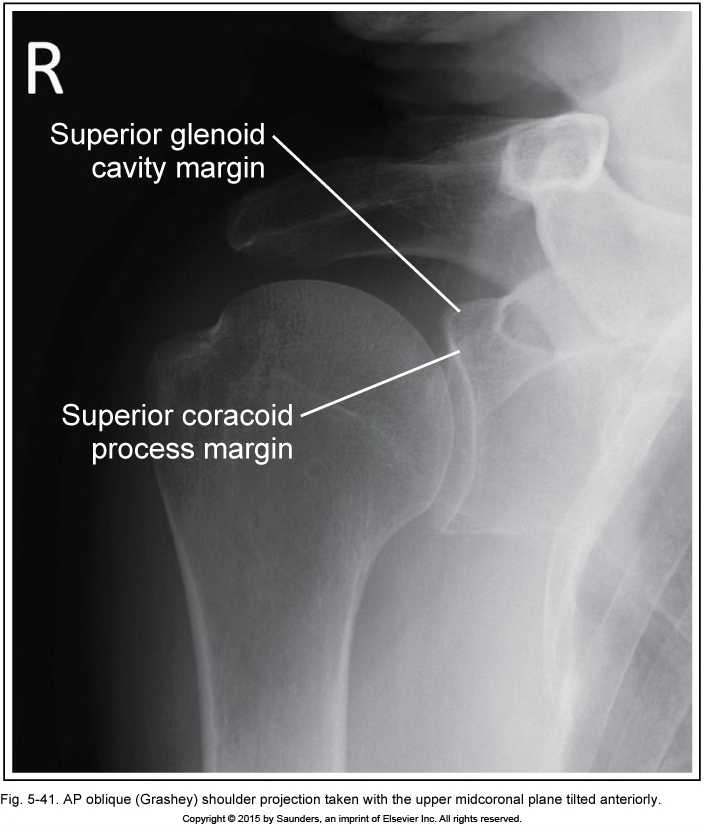

grashey

MCP tilt anteriorly

(coracoid process is below glenoid cavity)